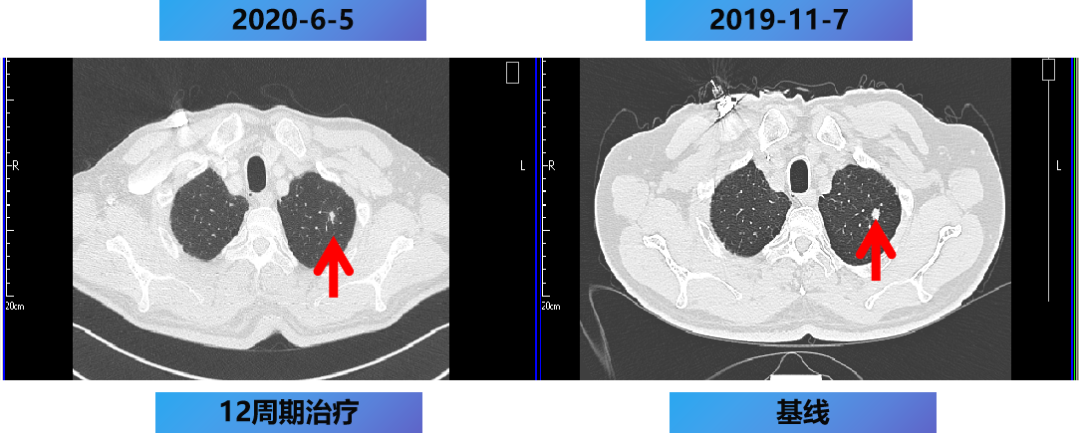

一线第1-12周期 CET+FOLFOX。

开始时间:2019-11-15至2020-5-2 每2周 一线治疗。

【治疗方案疗效评估】

MDT意见:肝转移灶可切除,肺转移灶缩小。

治疗目标:NED。

治疗策略:原发灶切除和肝转移灶切除,肺转移灶择期手术。